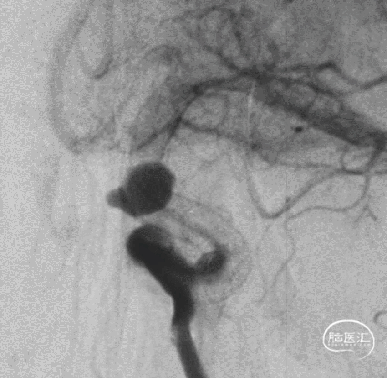

TB Plus 4/35

5、FD植入后,动脉瘤明显造影剂瘀滞,效果显著。

6、Tubridge Plus材料改进后通体显影,可以更好观察支架的贴壁性及术中打开情况,提高释放安全性。